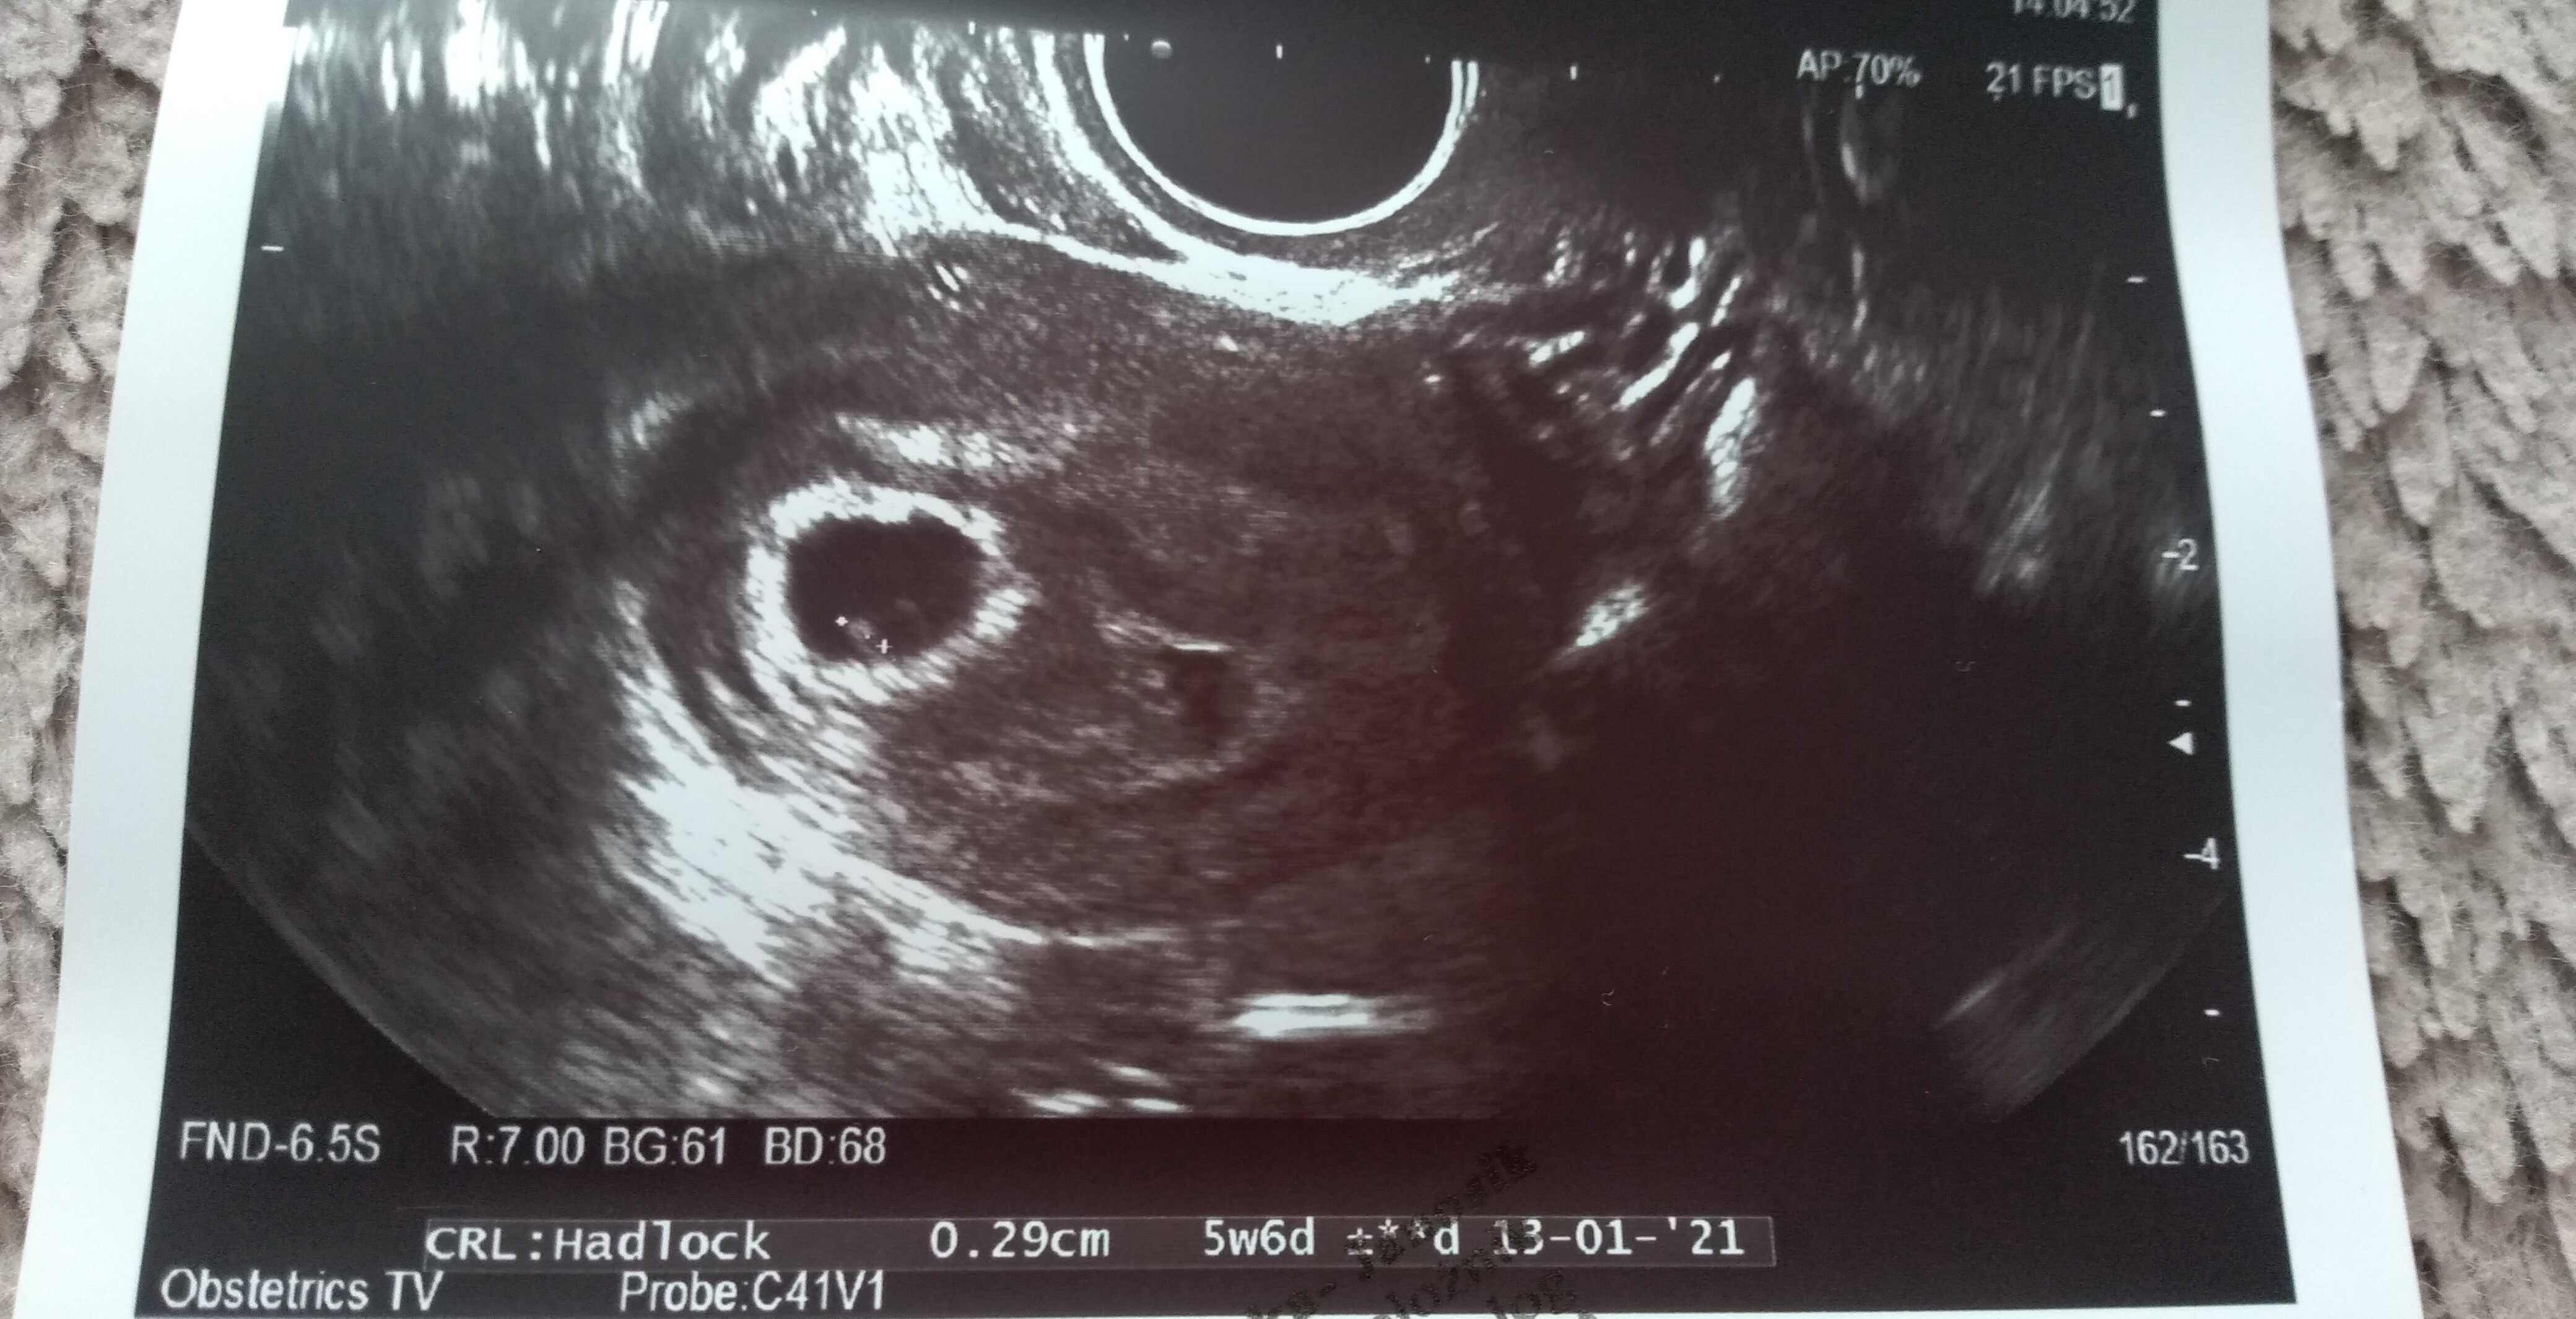

Hej dziewczyny, byłam na usg. Nie wiem co o tym myślećpowiedziała, że pęcherzyk ciążowy jest za mały na swój wiek. Ma 1,21 cm. Według aplikacji dziś 6+1

jest zarodek 2,9 mm. Serduszko bije 111/min. Nie puściła mi do słuchania tylko liczyła, widziałam jak faluje.

Jednak ciąża jakby jest młodsza o 2 tyg - usg pokazuje 4+2

Dodatkowo mam krwiaka większego dwa razy od pęcherzyka ciążowego - ma 8 na 5 i obok jakieś jeszcze mniejsze...

Różowa strzałka wskazująca to krwiak. Te duże coś na 5 cm to nawet już nie wiem z tego wszystkiego co to było